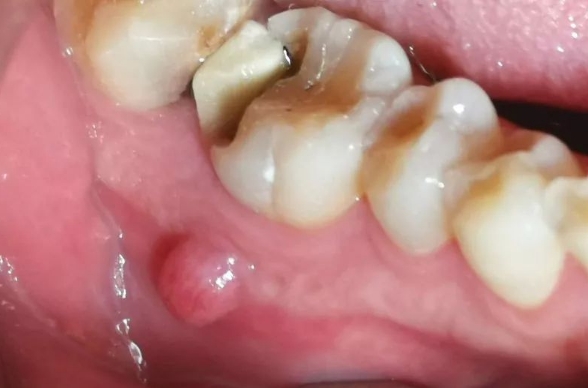

根尖炎分為急性根尖炎和慢性根尖炎。急性根尖炎通常表現(xiàn)為劇烈的疼痛、咬合痛、牙齒伸長感,患牙周圍的牙齦可能會出現(xiàn)紅腫、壓痛。慢性根尖炎可能癥狀不明顯,有時會在牙齦上形成瘺管,有膿液排出。